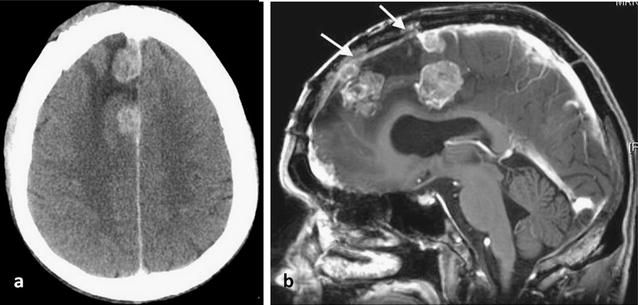

脑膜瘤是由覆盖大脑和脊髓的膜层而不是脑组织本身引起的肿瘤。肿瘤通常会持续数年而不是数周或数月,并且可以通过手术切除。从生物学上讲,大多数脑膜瘤是良性的,但有些可能具有侵略性且难以治疗,是当它们围绕神经(例如视神经,影响视力)或血管(例如从大脑排出血液的大鼻窦)时。脑膜瘤有残留就恢复发吗?在一项研究中,手术切除的脑膜瘤几乎有一半在20年后复发。这就是为什么需要定期监视的原因。尽管脑膜瘤患者远远不会完全“走出困境”,但在定期进行脑成像检查时,您可以过上正常的生活。相关阅读:一个万幸的选择--脑膜瘤患者德国治疗记

脑膜瘤手术后,您的外科医生将在手术后几天内安排术后扫描。该扫描有助于确保将肿瘤及其附着的膜(硬脑膜)完全清除。(如果不取出硬脑膜,可能会引起新的脑膜瘤。)

完全清除脑膜瘤和硬脑膜是避免复发的更佳方法。但是,即使完全切除了原始肿瘤,脑膜瘤在15年后仍会复发的概率为24%至32%。在大约95%的复发中,新的脑膜瘤在与以前相同的位置上生长。

在某些情况下,无法完全切除或切除。如果未完全清除脑膜瘤肿瘤,则很可能在10到20年内重新生长。